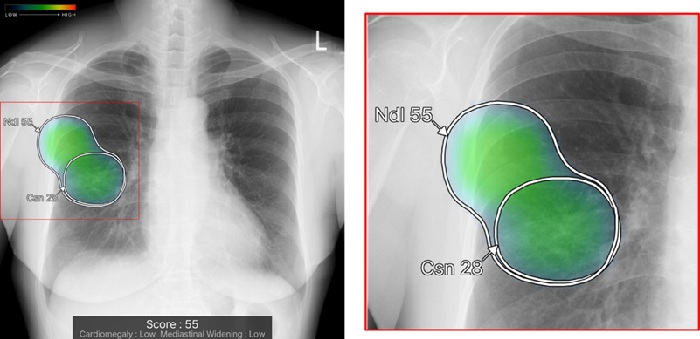

従来のバージョンでは、複数の異常所見を検出した場合、検出された異常所見のうち最も確信度が高い所見のスコアのみ表示していたが、新バージョンでは、検出領域に対応する所見名と確信度を示すスコアを個別に表示できるようにした。

また、対象所見が重なった領域で、所見ごとに独立した輪郭線を表示する。複数の異常所見が存在する箇所でも、それぞれの所見の範囲を明確に区別できるようになるため、詳細で正確な画像診断支援が見込めるとしている。